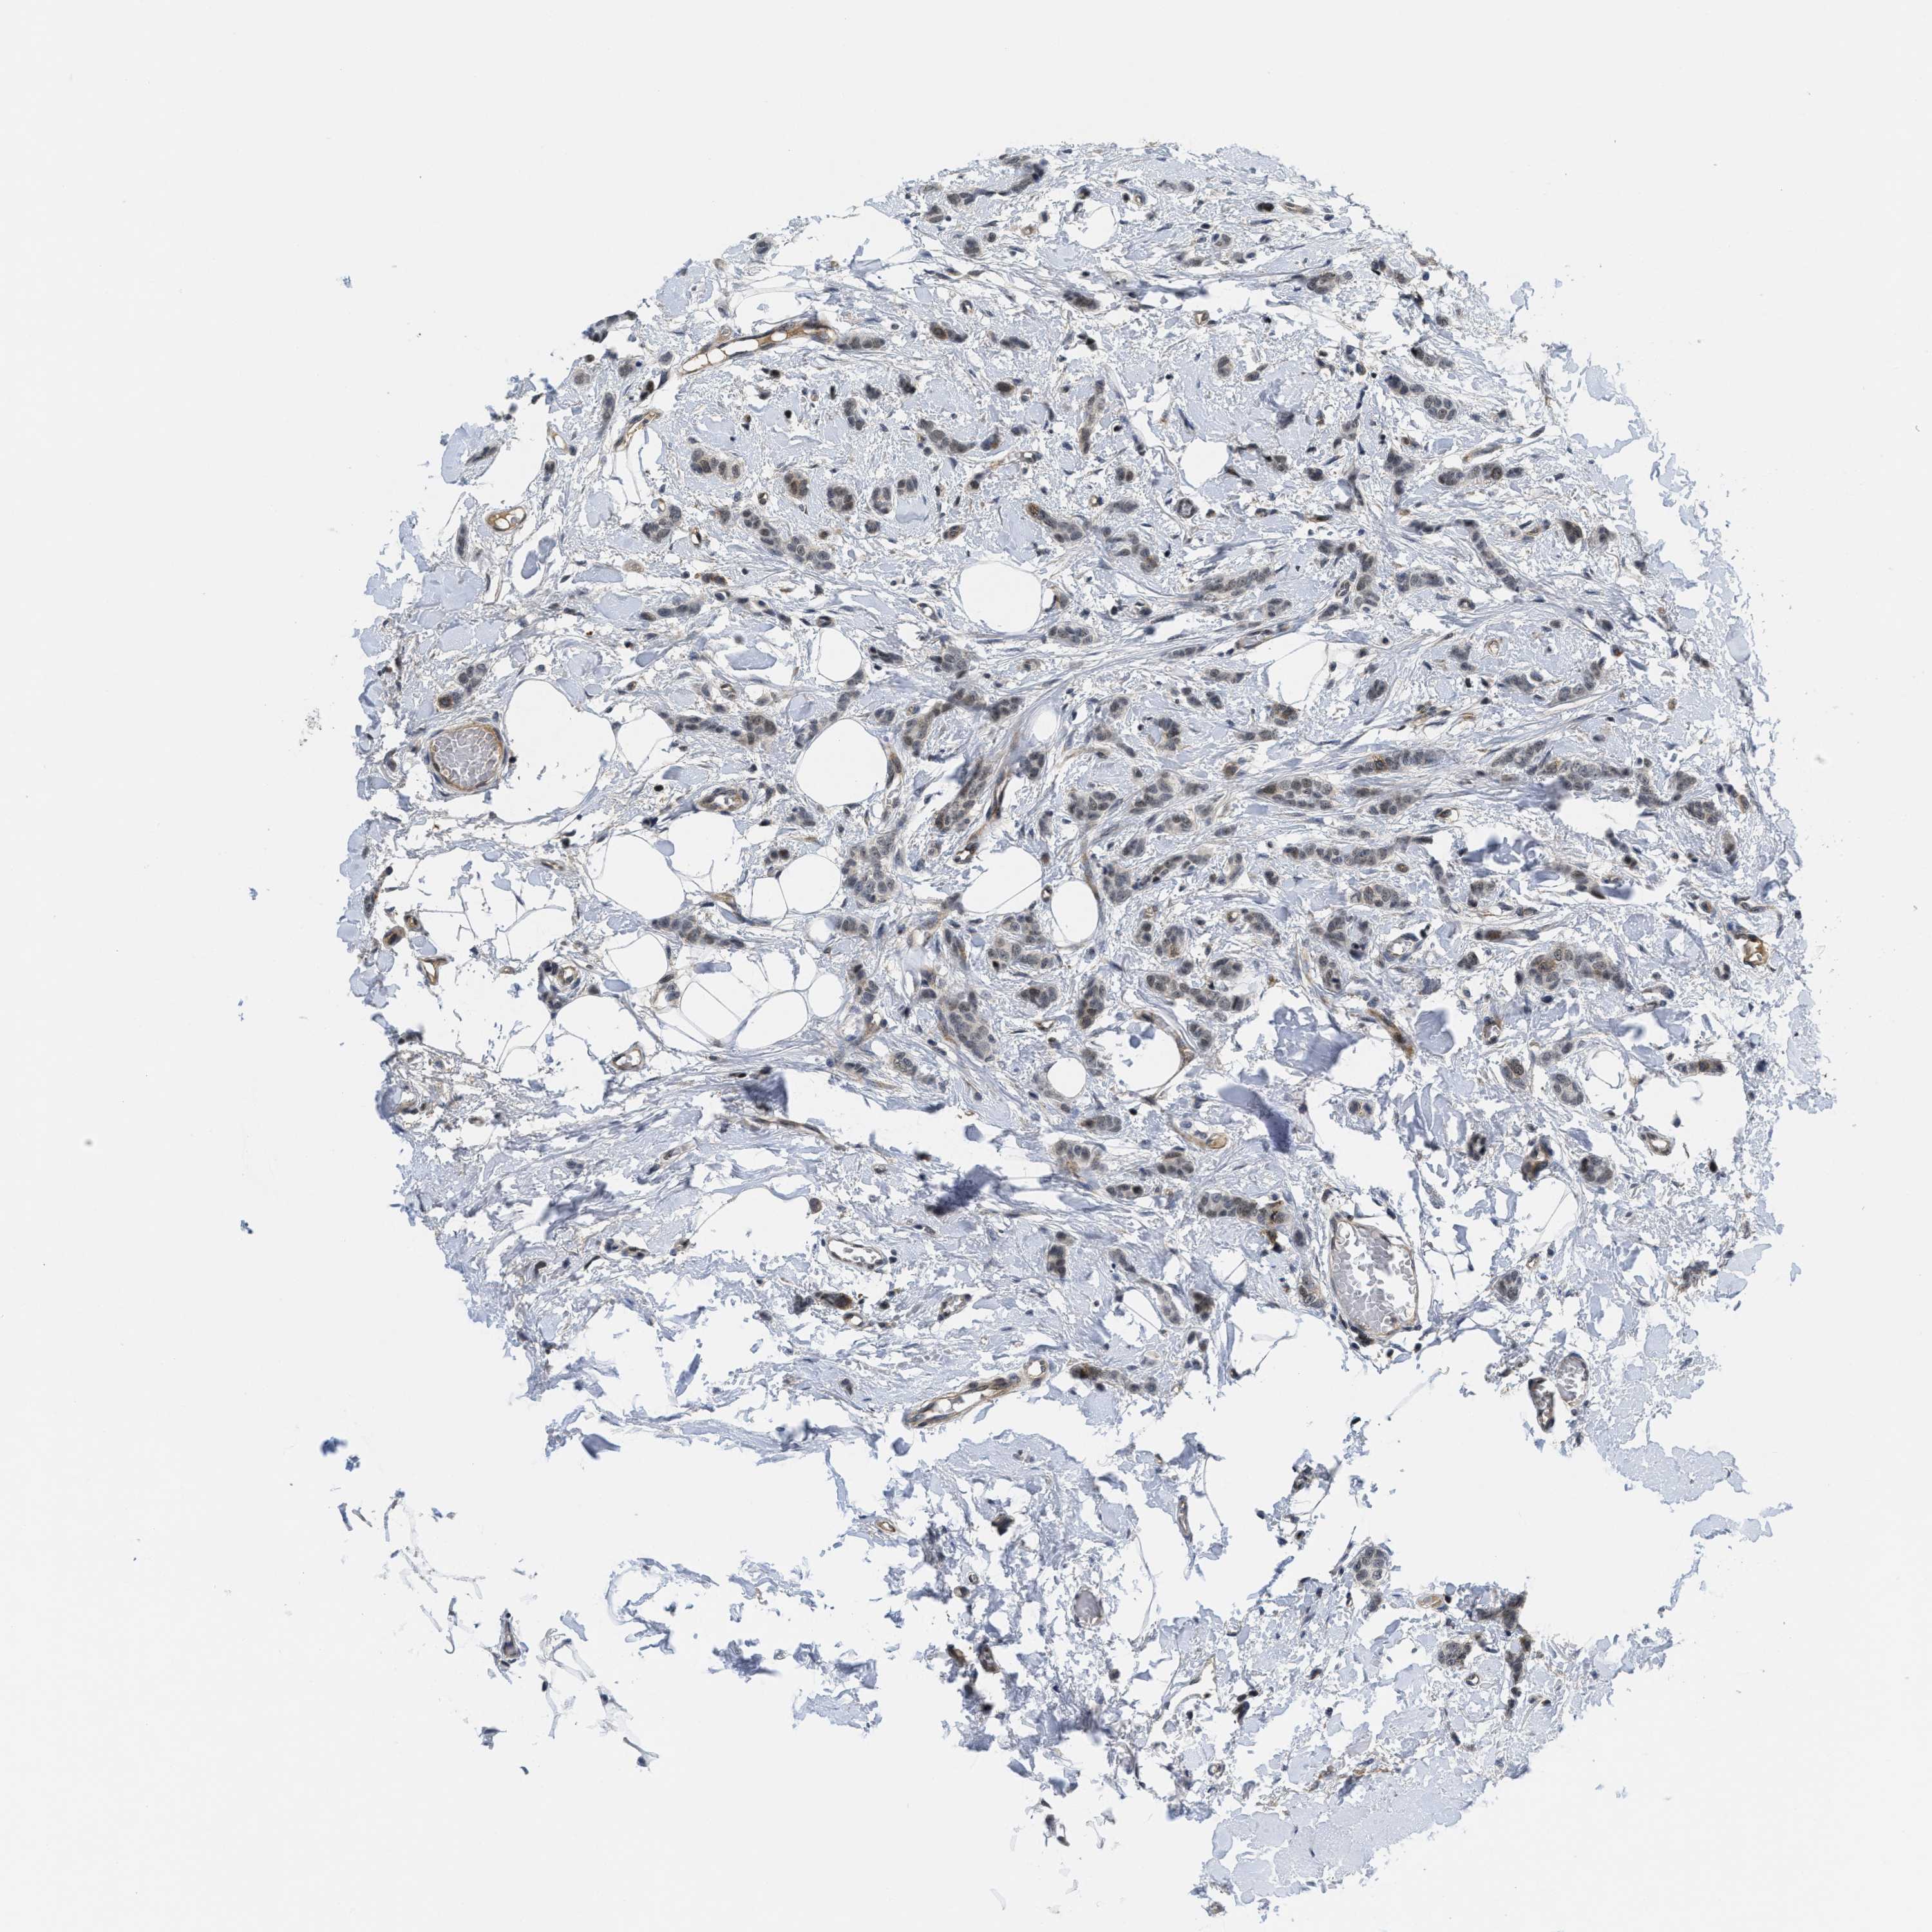

CANCER BREAST CANCER Show tissue menu

BRCA TCGA BRCA VALIDATION PROTEIN EXPRESSION